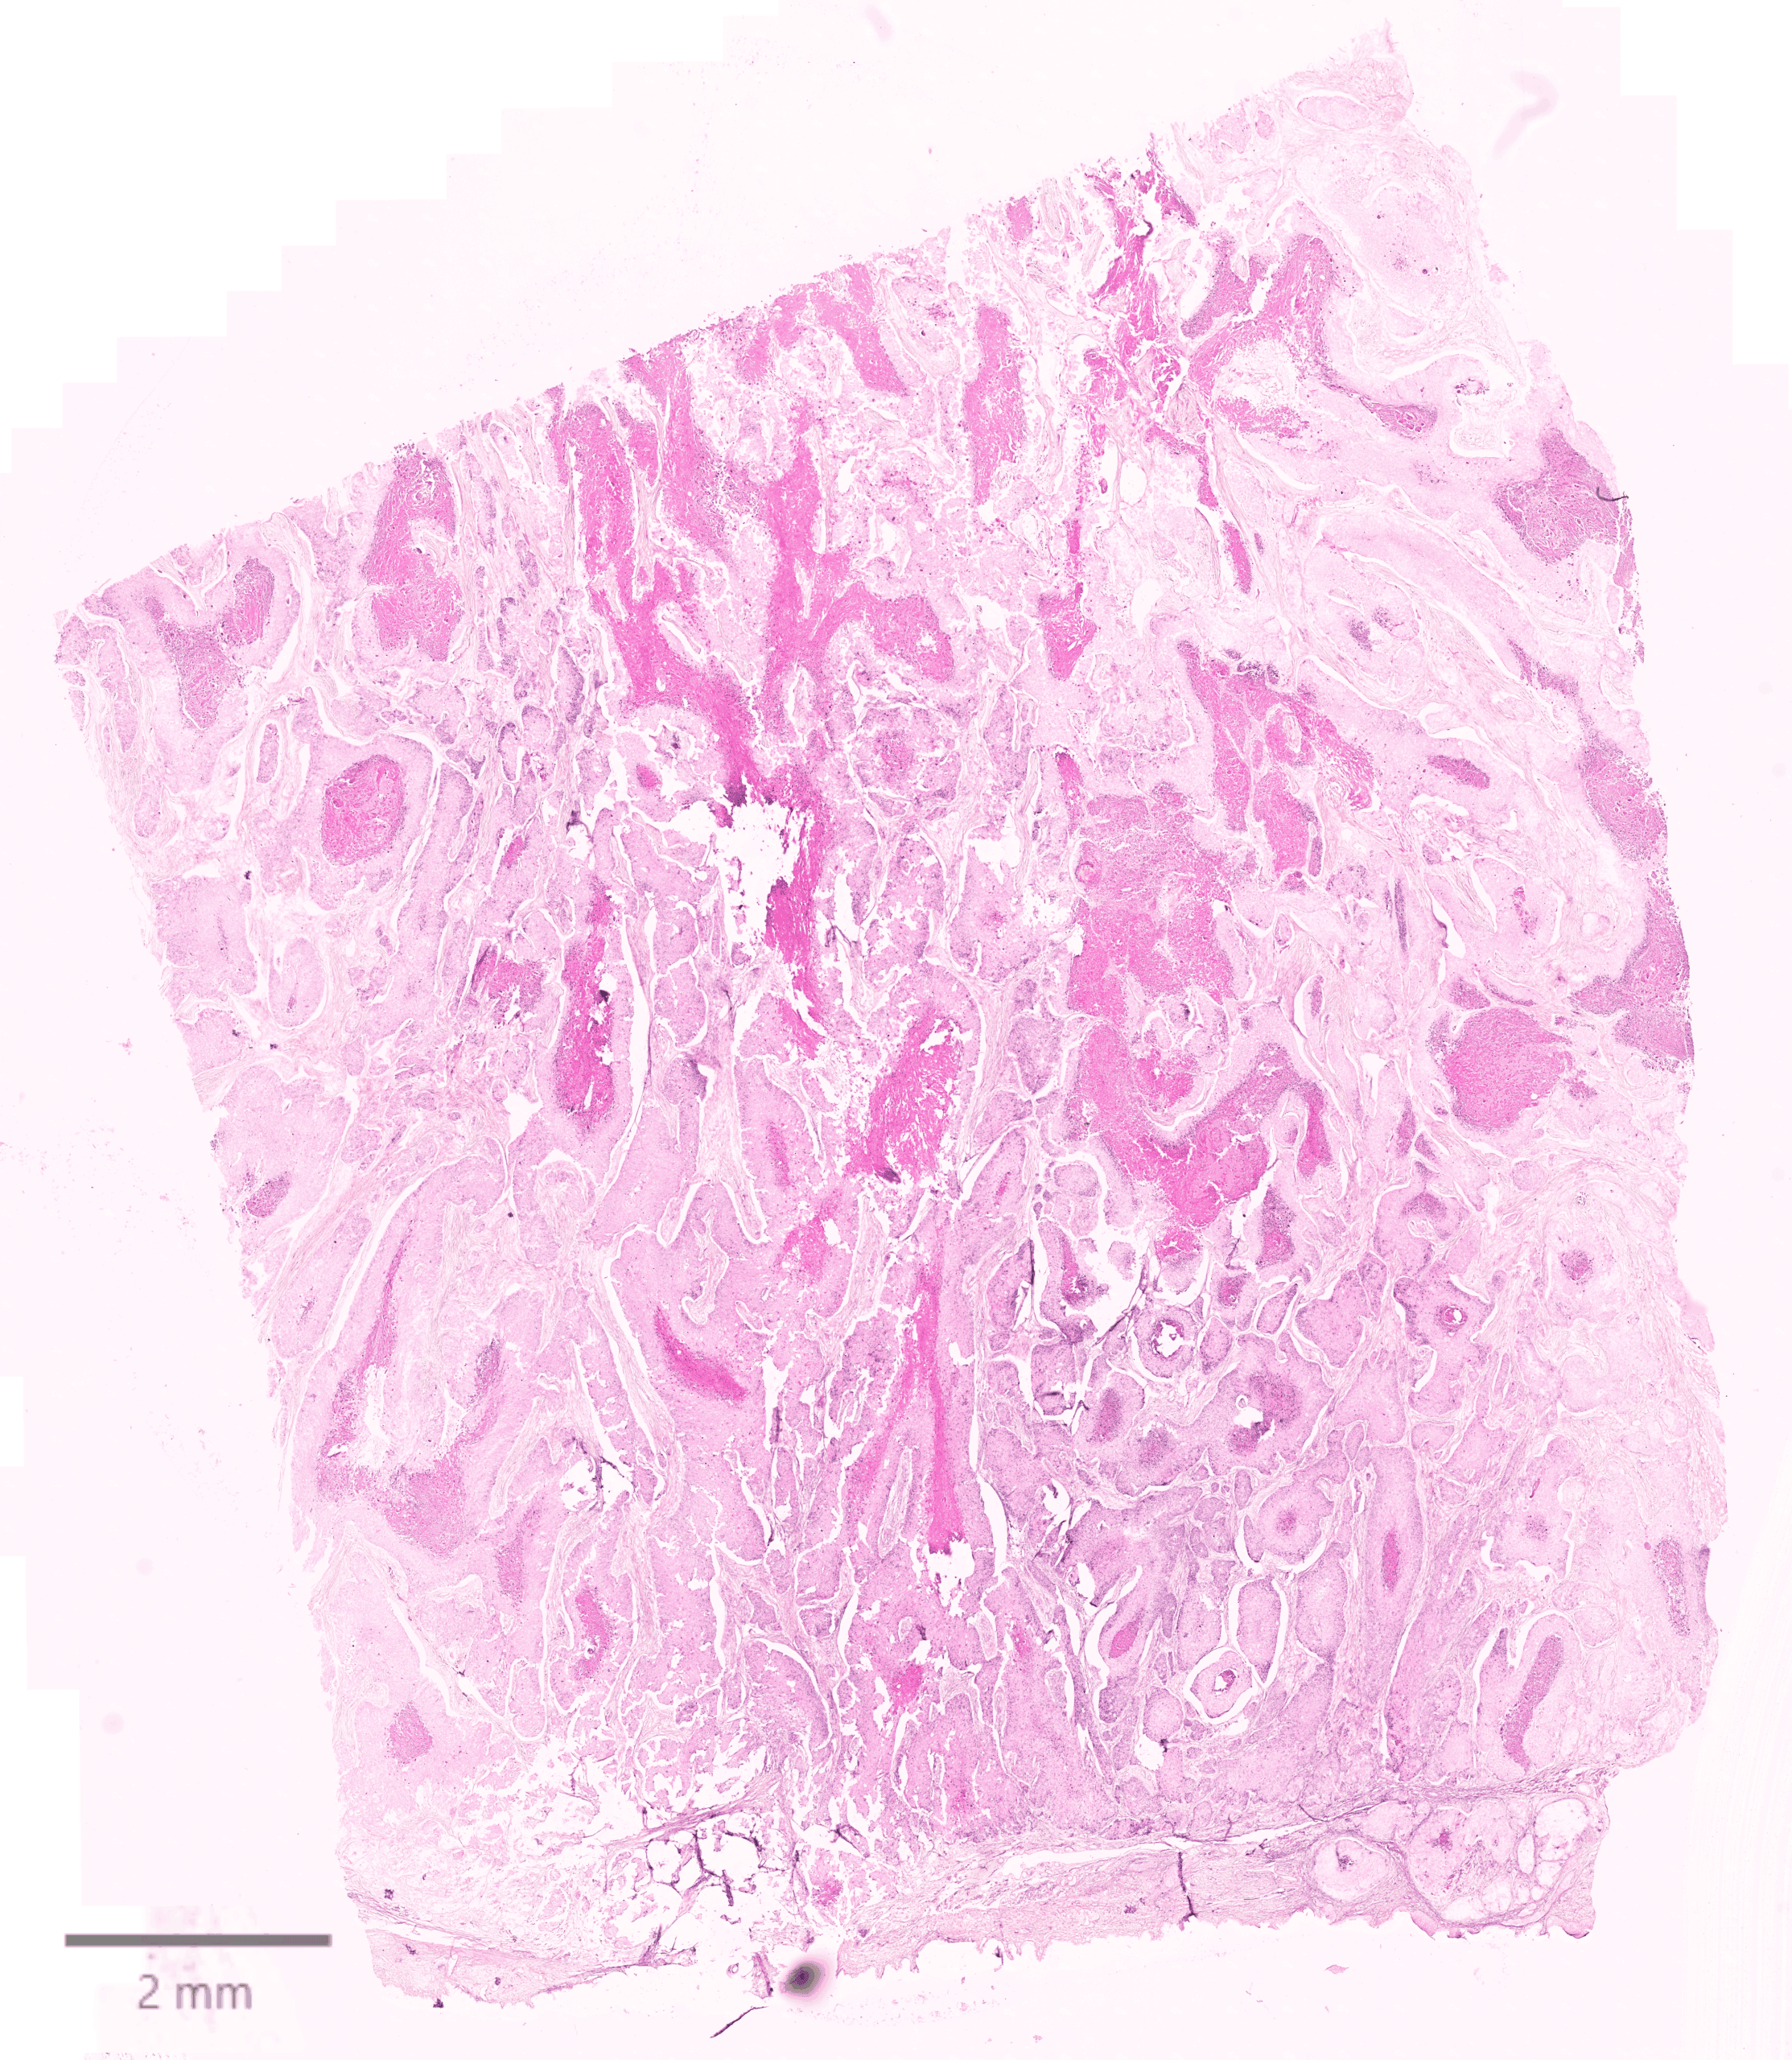

This dataset demonstrates the power of the CosMx SMI in characterizing clinical Squamous Cell Carcinoma samples. Utilizing CosMx Human Whole Transcriptome Panel, we analyzed a G2, Stage IV T3N2bM0 primary skin tumor from a 68 year old Caucasian male donor. By applying this high plex assay to FFPE tissue, we captured the entire protein encoding transcriptome over 18,000 genes at the highest subcellular resolution. By visualizing the distribution of the complete protein coding genes in these complex samples, researchers can identify unique molecular signatures and cellular interactions, paving the way for the next generation of precision oncology in skin cancer.

Whole transcriptome spatial data from skin tissue. The immunofluorescence image below shows CD45 in orange, CD68 in green, DNA in blue, membrane in gray and PanCK in yellow. An H&E image is also available for comparison.